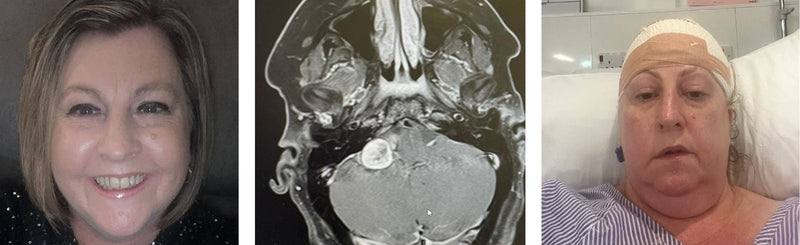

Amy Frankcom

5 min read